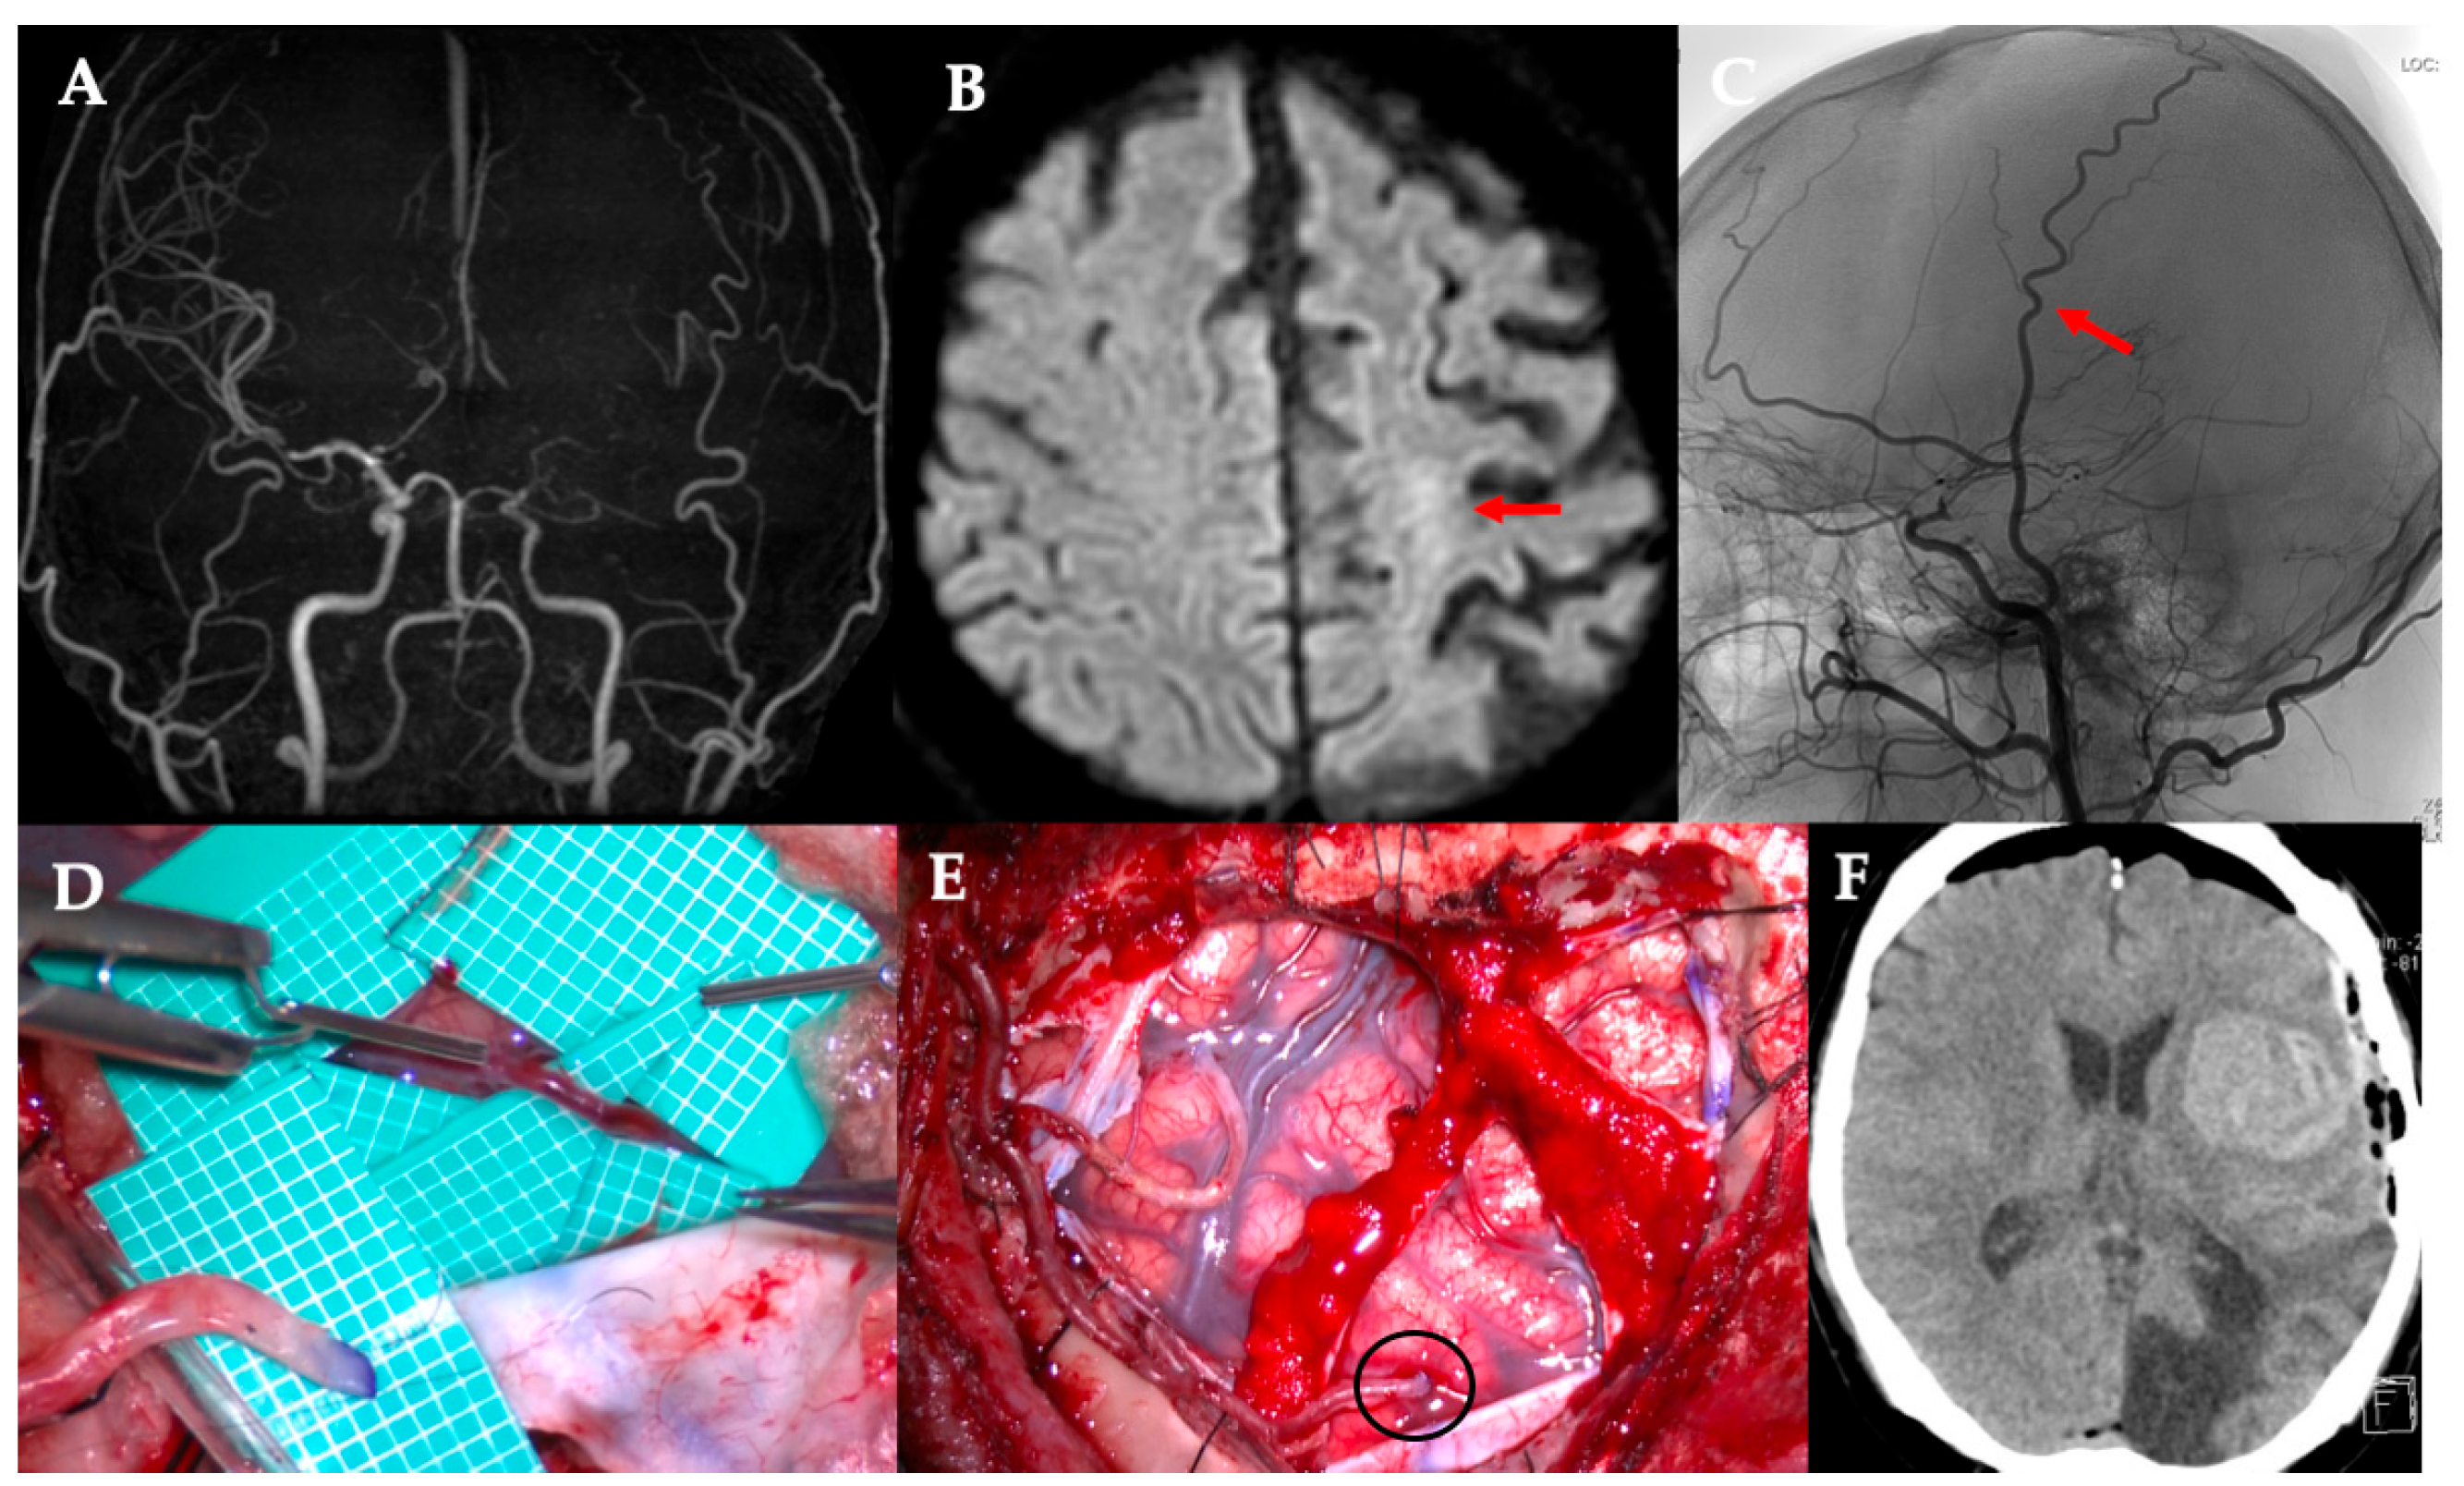

All five procedures were technically successful. Table 1 summarizes the key characteristics of each case. Preserving a side branch added an average of 5.6 min to the procedure (range, 3–11 min). In all cases, the bypass was patent on intraoperative ICG angiography, which demonstrated immediate perfusion of the distal MCA territory through the graft (Figure 2 and Figure 3). A schematic of this procedure is shown in Figure 4. The caliber of the STA side-branch donors ranged from approximately 0.5 mm to 1.1 mm (mean: 0.88 mm), closely matching the recipient artery diameters (0.4–0.9 mm, mean: 0.64 mm). No intraoperative complications (such as anastomotic thrombosis and vessel injury) occurred. The main STA trunk and any unused branches remained in situ to continue perfusing the scalp, and no signs of scalp ischemia were observed after sacrificing the side branch.

Figure 3. Case 2. The case of rapidly progressive MMD. (A) MRA. The main trunk of the internal carotid artery system has almost disappeared. (B) DWI. Right acute cerebral infarction occurred (red arrow) after the bypass surgery for the left cerebral hemisphere. (C) The side branch of the right STA parietal branch (black arrow) is anastomosed to M4 of the frontal lobe (black arrowhead), while blood flow is preserved in the main trunk (red arrow). MMD, moyamoya disease; MRA, magnetic resonance angiography; DWI, diffusion-weighted image; STA, superficial temporal artery.